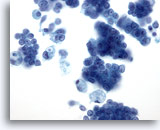

Figure 28: Breast FNA, Ductal carcinoma in situ. This is a cellular aspirate showing clusters of tumor cells, single malignant cells and foamy macrophages. Ductal carcinoma in situ (DCIS) often shows myoepithelial cells overlying the malignant cell clusters. Tumor cells tend to be clustered rather than single as in invasive tumor. In addition, tubular structures are not associated with DCIS. Comedo DCIS is characteristically associated with necrosis and calcium. 40x

Figure 28

Breast FNA, Ductal carcinoma in situ.

This is a cellular aspirate showing clusters of tumor cells, single malignant cells and foamy macrophages. Ductal carcinoma in situ (DCIS) often shows myoepithelial cells overlying the malignant cell clusters. Tumor cells tend to be clustered rather than single as in invasive tumor. In addition, tubular structures are not associated with DCIS. Comedo DCIS is characteristically associated with necrosis and calcium.

40x